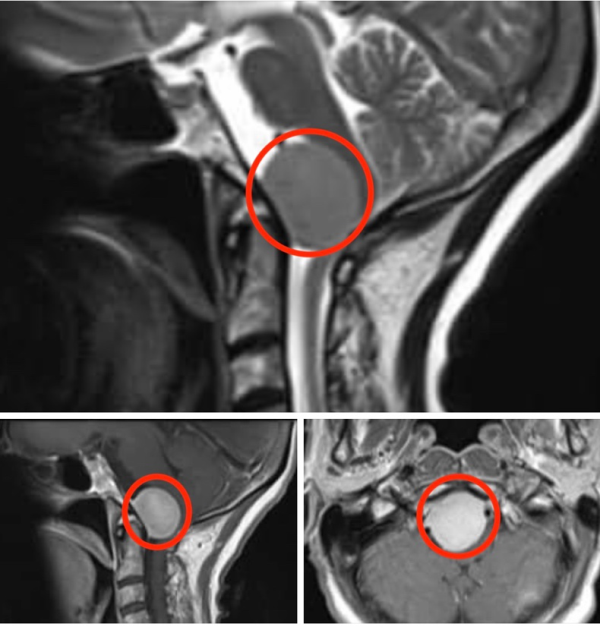

怀孕期间诊断出枕骨大孔区脑膜瘤怎么办?一位34岁的女性患者,在她的妊娠中期确诊脑膜瘤,经原外侧入路成功切除。...

脑膜瘤可以在怀孕期间出现,而且枕骨大孔脑膜瘤少见,本文报告了一个成功治疗期间怀孕的案例...